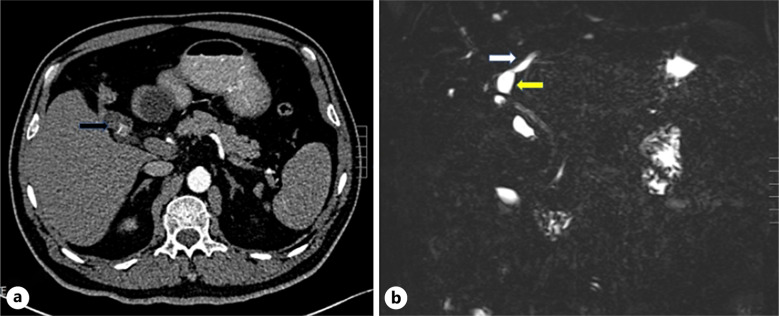

Case presentation: Seven aviation pilots who underwent laparoscopic cholecystectomy in recent 5 years were reviewed, and 3 cases who developed long-term PCS because of variations of bile duct were presented. Variations of bile duct included existence of accessory extrahepatic bile, absence of common bile duct, and absence of cystic duct. Long-term PCS was characterized as epigastric dull pain and diarrhea or sparse stool, and became aggravated when resuming trainings of flight stimulations. Dietary adjustment and oral antispasmodic or cholagogic drug therapy, combined with relieving apprehensions after surgery, helped them recover well and resume flight.